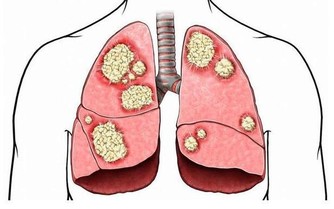

中醫認為一切病先是神病,然後是氣病,再到血病,最後才到什麼呢?形病。疾病先從生命無形的部分,即從精神、信息的層面開始出問題;第二個階段,到氣的部分,能量格局和運行規律發生紊亂;第三個階段,到有形的疾病層面。很多人的病,其源頭是某種很大的煩惱、很大的怨恨,或者很多他們無法解決的困惑。很多時候,病是因為他們不願意去面對、澄清、解決。